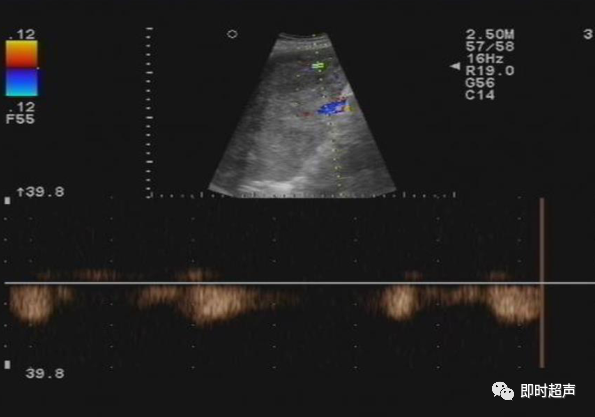

• GIST的发病机制与KIT信号通路的激活有关。• KIT是一种酪胺酸激酶跨膜受体蛋白,未经“装配”过的KIT蛋白是一种非活化的单体,参与细胞膜形成。几乎所有GIST都表达了KIT蛋白,而且大多突变的KIT基因保留了表达KIT蛋白的特性。c-kit内的突变主要见于恶性病例,特别是外显子11的点突变,还有外显子9、13和17,可以导致本质的或配体独立的c-kit激活,引发细胞的无序增殖和凋亡。这些具有功能的突变是GIST发病机理的关键,并且与肿瘤的恶性程度和预后较差相关。• GIST约75%发生于50岁以上老年人,中位年龄为58岁,无明显差异。• 可以发生在消化道从食道到肛门的任何部位,偶尔可原发于网膜、肠系膜和腹膜后,约50%发生在胃,25%发生在小肠,不足10%发生于食管、结肠及直肠。大体观察:肿块多境界清楚,类圆形,结节状,部分有假包膜。切面灰白、灰红,质韧,部分质嫩呈鱼肉状,伴有出血、坏死、囊性变。• 肿瘤组织主要由两种细胞组成,一种为长梭形细胞,细胞质丰富,嗜酸性,细胞核呈梭形或杆状;另一种为上皮样圆形或多角形细胞,细胞肥胖,胞质少。两种瘤细胞常呈束状、编织状或旋涡状排列。• 部分病例细胞异型明显,核分裂象增多,可见病理性核分裂象和瘤巨细胞。梭形细胞界不清楚,胞质丰富,淡染,轻度嗜伊红或略嗜碱,可有纤细、长梭形、短梭形或胖梭形、卵圆形,可见核仁。细胞核两端钝圆,部分病例胞质呈空泡状,位于核一端形成核端空泡胞,多呈交叉束状、旋涡状、席纹状及栅栏状排列。上皮样细胞胞浆丰富或透亮,多呈弥漫片状、束状或巢状排列。肿瘤间质可有出血、囊性变、坏死及黏液变,可见炎性细胞浸润。CD34抗原是一种115kd的糖基化蛋白,50%~80% GIST的CD34表达为阳性,CD34对鉴别GIST和典型的平滑肌瘤,神经鞘瘤还是非常有用的标记物,因后两者的CD34一般是阴性的。但CD34在诊断GIST上其特异性受到限制,一般情况下CD34多与CD117联合应用,方能提高GIST的诊断率。• 与肿瘤大小、发生部位、肿物与肠壁的关系以及肿瘤的良恶性有关。• 肿瘤较小者(直径小于2cm)常无症状,往往在体检和其它手术时无意中发现。• 肿瘤发生于胃肠道腔内时大多表现为呕吐、腹痛及消化道出血,而发生于胃肠道腔外的则主要表现为腹部包块。• 最常见的临床症状是中上腹部不适、腹部肿块及便血。• 对于临床发现的消化道(包括肠系膜、网膜、后腹膜)实体肿瘤,在排除其他常见肿瘤后,才考虑GIST。目前,诊断GIST有三条标准:③肿瘤组织具有梭形细胞和上皮样细胞两种基本细胞成分的病理学特征。这是诊断GIST金标准。CD117阳性者或CD117阴性而CD34阳性者,且伴平滑肌和神经双向分化或无分化者,可诊断为GISTs;以Desmin和SMA强阳性,而CD117阴性诊断为平滑肌肿瘤;以S-100阳性,CD117、Desmin、SMA均阴性诊断为神经鞘瘤。• GISTs的分型与组织学良恶性的关系:研究证实GISTs非单一分化的肿瘤,具有多向分化。• 当前GISTs的良性、交界性和恶性判断标准多参照Amin等提出的标准:②交界性:核分裂<5/50HPF,但肿瘤>5cm;• 另外研究显示,平滑肌型大多数为良性,少数为交界性和恶性,神经源型为恶性,双向分化亚型和未分化型为交界性和恶性,提示GISTs的分化型与其良恶性之间有一定关系。• 胃间质瘤早期多局部侵犯,后期出现肝转移和腹腔内种植,小肠间质瘤早期即可出现转移• 主要有超声扫描(检出率30%左右)、纤维内镜、超声内镜、CT、MRI、普通X• 线检查(胃肠钡餐造影、小肠插管气钡双重造影)、选择性血管造影检查等。• 不同部位的GIST,各种检查方法的敏感性不同。以CT检查为佳,尤其是螺旋CT,分辨率最高,可以三维重建,直接显示肿瘤大小、形态、密度、内部结构、边界,对邻近组织的侵犯也看得很清楚,同时还可观察其他部位的转移灶,有利于分期、鉴别与诊断。• MRI具有多轴成像及反映肿瘤内部成分的优点,尤其是动态扫描及各种新的扫描系列的出现更使其可以普及应用。• DSA检查对于GIST,特别是有消化道出血的患者更有价值。• 上述影像学检查表现并非特异性,与胃肠道平滑肌肿瘤、神经源性肿瘤鉴别困难。明确诊断要依赖病理免疫组化等手段。• 超声图像特征 肿物体积较小者(直径< 5. 0 cm )多为实性病变, 呈类圆形, 边界清晰, 内部回声多为较均匀的低回声。• 肿物体积较大者(直径> 5. 0 cm ) 多为混合性病变,呈不规则圆形或分叶状, 多数边界尚清晰, 以实性为主的病变内部为不均质中低回声伴不规则液性区及斑点状强回声; 以囊性为主的病变囊壁较厚,有分隔, 部分囊腔内可见点状、团状低回声。CDFI显示肿物实质回声内血流均较丰富。病例1:患者男, 62岁。自扪腹部包块2月余,包块增大20天就诊。查体:腹部平坦,无腹壁静脉曲张,无胃肠型及蠕动波,腹肌软,剑突下5cm处及左肋缘下可触及一质韧包块,大小约15*12cm,活动度差,边界尚清,包块深压痛,全腹无反跳痛。化验检查AFP:3.66(1.09-8.04)ng/ml,CEA:2.85(0-5)ng/ml。体格检查:一般情况良好,全腹软、平坦,腹部无压痛。超声检查:患者仰卧位时左上腹于胰尾前方可见一大小约6. 1 cm ×5. 8 cm ×5. 3 cm实性均质低回声,形态规则,包膜完整,边界清晰,活动度大;右侧卧时,肿块移至胰头右前方(图1) ;于其内探及丰富血流信号。体格检查:一般情况良好,腹丰满,上腹部有轻压痛,未扪及明显肿块。超声检查:患者仰卧位时左上腹于胰尾前方、脾门处可见一大小约10. 0 cm×8. 8 cm×7. 6 cm 实性低回声(图2) ,形态规则,包膜完整,边界清晰,肿块活动度大;右侧卧时,肿块移至左肝下间隙,回声尚均质;于其内探及较丰富血流信号(图3) 。图3 腹腔低回声肿块位于左肝下间隙,于低回声肿块内探及较丰富血流信号向壁外生长的胃肠道间质瘤, st为胃腔,箭头所指为胃壁, T为向外生的肿瘤• 胃间质瘤的定位准确率要高于十二指肠及小肠间质瘤,这主要是因为胃的解剖位置相对固定,且通过饮水使胃腔充盈,可清晰的显示胃壁的各层结构及肿块与胃壁的关系。肿块多表现为粘膜下、肌层或浆膜下低至中等回声团块,可向腔内、腔外或腔内外生长。但当肿瘤较大或浸润周围脏器时,超声定位仍有困难, 因此,超声如发现上腹部肿块且怀疑来源于胃者,应尽可能嘱其饮水充盈胃腔,并多角度、多切面观察肿块与周围脏器的关系,以提高定位的准确性。• 十二指肠间质瘤的定位亦较准确,但降部的外生性肿块常与胰头粘连而误诊为胰腺肿瘤回声均匀且位置较深的间质瘤亦可能误为胰头周围淋巴结。• 空、回肠间质瘤常因肿块较大,多发,位置不固定而难以定位,往往误诊为腹、盆腔或腹膜后肿瘤,超声检查如发现肿块局部肠壁增厚,肿块与肠道随呼吸同步运动时可作出定位诊断。• GIST的声像图表现有助于其良、恶性的鉴别:良性肿瘤多体积较小,圆形或椭圆形,回声均匀,边界清晰。恶性肿瘤多较大,呈不规则分叶状,回声不均匀,内部易出血、坏死、囊变。• 肿瘤长径与肿瘤内部是否出现无回声区在良、恶性病变之间的差异有统计学意义,是判断良恶性的有效征象。• 如以肿瘤长径>5cm为诊断恶性标准,其敏感性、特异性及准确性均较理想。超声可为临床提供胃肠道间质瘤的部位、大小、边界、回声等较多有用信息,一部分病例可作出定位、定性诊断,并可在术后或复发患者药物治疗期间对其进行动态观察;CDFI方便快捷、无需造影剂即可对间质瘤周边及内部血流进行观察,可为临床医师提供肿瘤血供情况。但未发现腹腔或肝脏转移时,超声判断胃肠道间质瘤性质有一定难度。• 目前临床上对GISTs的治疗效果并不十分满意。治疗仍以手术为主,对无法手术切除或已有转移的GISTs患者进行甲磺酸伊马替尼化疗。• 手术方式取决于肿瘤大小、部位和术中冰冻切片结果等。• 发生在胃的间质瘤,可首选胃大部切除术;发生在十二指肠的间质瘤可行保留胰头的十二指肠切除术或胰十二指肠切除术;发生在小肠的间质瘤可行肿瘤肠段切除术;发生于结肠的间质瘤可行左半或右半结肠切除术;发生于直肠的间质瘤可行肿瘤局部切除术。一般情况下无需淋巴结清扫。• 术后随访监测,复发者单个病灶可考虑手术切除;多发或转移特征者应试行甲磺酸伊马替尼化疗,并监测肿瘤大小及数目的改变。• 随着分子靶点药物进入肿瘤临床,一种小分子化合物———酪胺酸激酶受体抑制剂,美国称为Gleevec,欧洲叫做Glivec(格列卫),在治疗GIST和慢性粒细胞白血病方面有其独特的作用。已知细胞膜表面上皮生长因子受体酪胺酸激酶抑制剂大致分为两大类:一类是小分子化合物;另一类是特异性抗体。利用抑制酪胺酸激酶的活性,对处于增殖期状态的病变具有治疗的作用。Glivec在体外、体内和细胞水平都可强烈抑制酪胺酸激酶的活性,是干细胞因子(SDCF)受体KIT的强抑制剂。• Glivec推荐用量为400mg(4片),每日一次, 3个月为一疗程。如服3个月后无效可加至600mg/d~800mg/d(6~8片)[18];若仍无效果不再增量应停止治疗。• Glivec治疗进展转移的GIST总有效率为50%左右,比传统化疗有效率高十倍以上;肿瘤生长控制率达80%以上,起效最快在服药后24h之内,使症状改善如疼痛缓解;平均起效时间为13周(约3个月)。患者体力状况改善是又一突出效果。2/3患者治疗后无症状可如健康人生活工作。• Brainard等研究发现间质瘤预后差的前两位因素为肿瘤大小和核分裂象,故对于间质瘤直径>5cm和核分裂象>5/50HPF的患者应给予口服Glivec。最近,Liu报道口服Glivec治疗可使85%患者的病情得到控制。